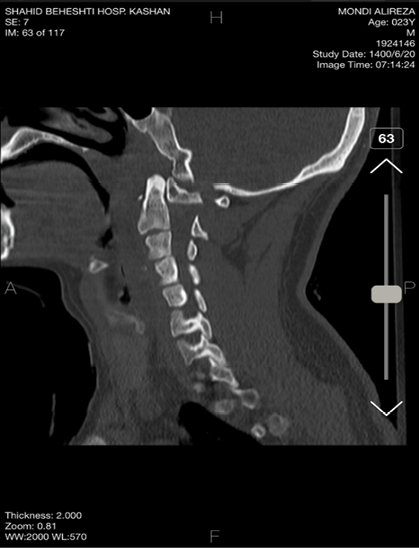

The patient was discharged with a cervical collar after three days. He returned for a follow-up visit after one week, during which we conducted a cervical CT scan (Figure-6). In the CT scan, the impactor showed to be placed appropriately, no sign of displacement was evident. At this point, tracheostomy was removed, the patient reported significant improvement and no longer experienced cervical pain.

Figure 6. Cervical CT images after 1 week of surgery. The impactor showed to be placed appropriately, no sign of displacement was evident.